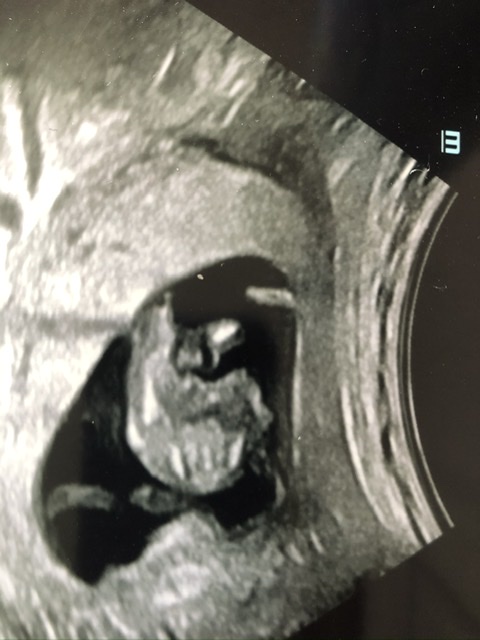

Hi, this is the best image from my scan yesterday. During scan I thought I saw nub - long bright white line - but couldn’t work out angle. Unfortunately, it’s not in the picture - but I wondered if the two tiny lines circled might be the end of it poking out? If so, could anyone hazard a guess as to sex? Thanks in advance!